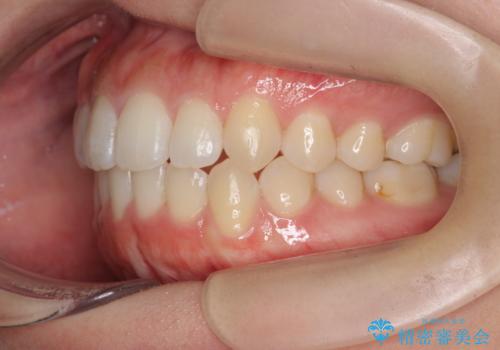

前歯のすれ違い インビザラインで行うマウスピース矯正

- 前歯のガタつき、でこぼこ、前後が逆になっている噛み合わせの改善を求めて来院されました。

治療の装置が目立たず歯ブラシのしやすいマウスピース矯正インビザラインでの治療を計画します。

20時間/日の装用時間をしっかりと守っていただき、きれいな歯並びを手に入れることができました。